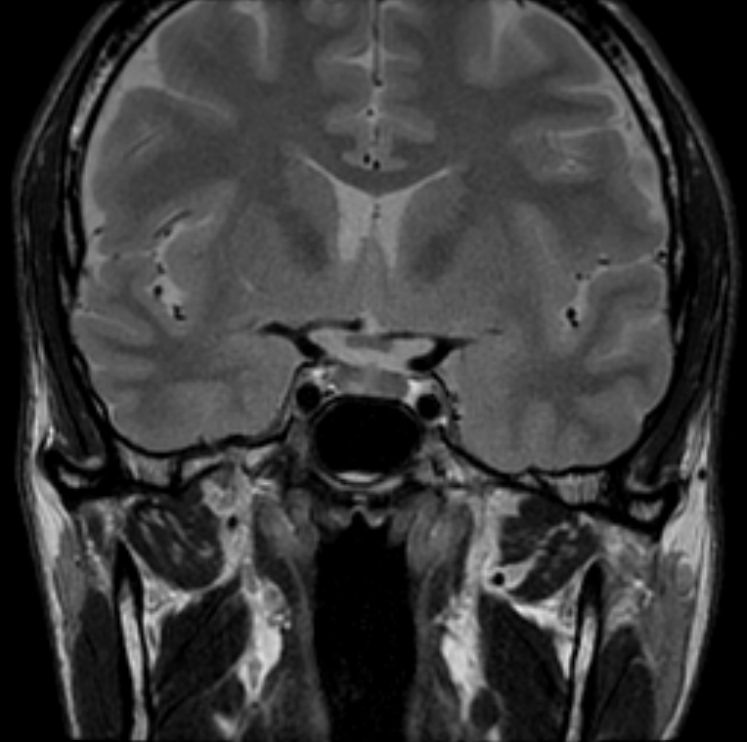

МРТ гипофиза

Магнитно-резонансная томография гипофиза – важный метод исследования, который позволяет оценить состояние гипофиза.